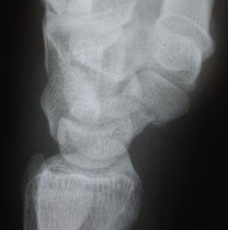

Normale Einstellung (links) und Spezialaufnahme (rechts)

Zur genauen Beurteilung der Bruchstücke und Planung der Operation kann ergänzend eine Computertomographie in Längsrichtung des Kahnbeins durchgeführt werden.